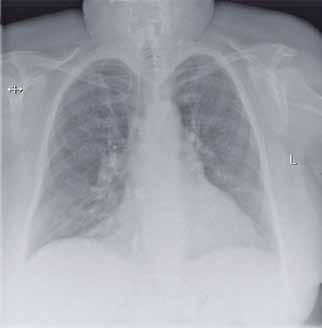

Na zdjęciu RTG klatki piersiowej (ryc. 5.1) pola płucne z cechami prze wlekłego nieżytu oskrzeli, bez zmian ogniskowych. Sylwetka serca powiększona. Naczynia we wnękach poszerzone. Przepona i kąty prze ponowo żebr owe wolne.

RTG klatki piersiowej